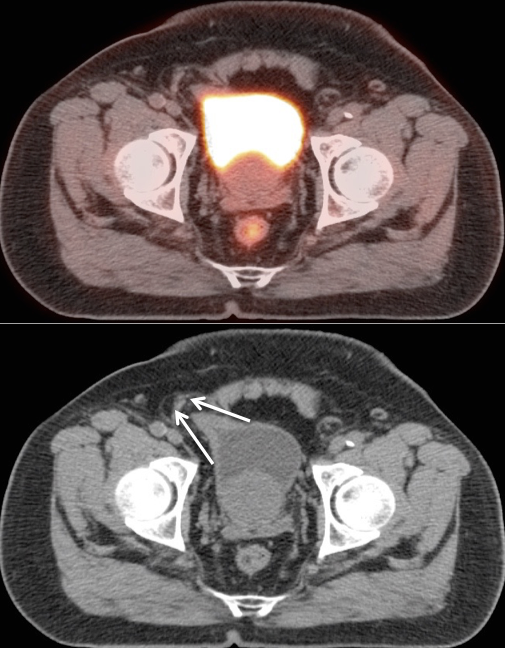

Bladder Hernia

While the CT appearance of this finding should never be missed, its striking PET appearance has led more than one PET/CT reader astray.

Usually, the supero-lateral margin of the bladder will be seen partially entering the inguinal canal. Occasionally, a significant segment of the bladder may extend deep into the hernia defect.

Caveat: Never be duped by an unusual focus of intense metabolic activity anywhere in the body. Always rule out every possible non-neoplastic explanation before raising the specter of cancer.